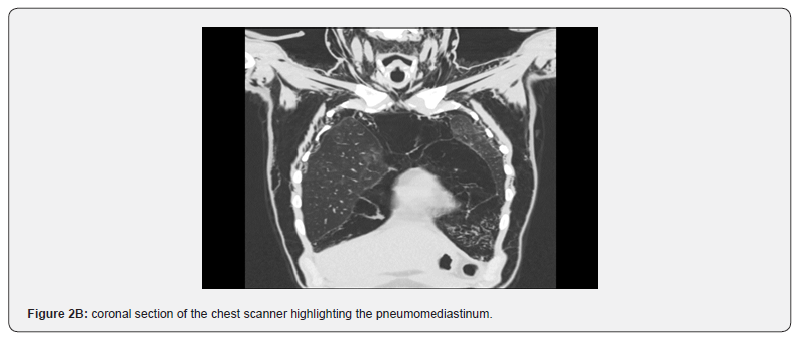

A 30-year-old man was admitted to the emergency room for stage 3 dyspnoea of the MRC classification, with signs of chest muscle tightness, fever at 39° and sweating. After conditioning and stabilizing the patient on the ventilatory level, the physical examination showed crackles on pulmonary auscultation, heart sounds were well perceived, there was no abnormality in the rest of the ‘physical examination. Oxygen saturation was low at 89% in room air. Blood pressure was 110/08mmHg. Chest x-ray showed diffuse nodular opacities in both lung fields as well as reticular lines (Figure 1). Chest CT showed left basal consolidation and scattered ground glass hyper densities in both lungs (Figure 2A and 2B). The biological assessment showed white blood cells at 13,000 e/mm3, a CRP at 100mg/l. A rapid test for positive HIV infection that has been confirmed by serology after patient consent. Normal liver and kidney function.

The realization of the thoracic scanner is often necessary especially if the patient presents a chronic pathology, or if there is a suspicion of oesophageal rupture. It shows the pneumomediastinum in a precise way where air is detected over the entire anatomical tract of the mediastinum [16]. Esophageal transit with water-soluble fluids is necessary if there is a suspicion of esophageal rupture, it shows extravasation of the contrast product. The evolution of spontaneous pneumomediastinum is generally towards resorption in 48 to 96 hours by the passage of air into the bloodstream, this passage is accelerated if the patient is put on oxygen thanks to the theory of the diffusion of nitrogen [17]. The management of pneumomediastinum depends on the severity of the clinical presentation and the volume of it on the chest CT scan, as well as possible complications which may be compression of adjacent structures or air infiltration to the different spaces. life-threatening.